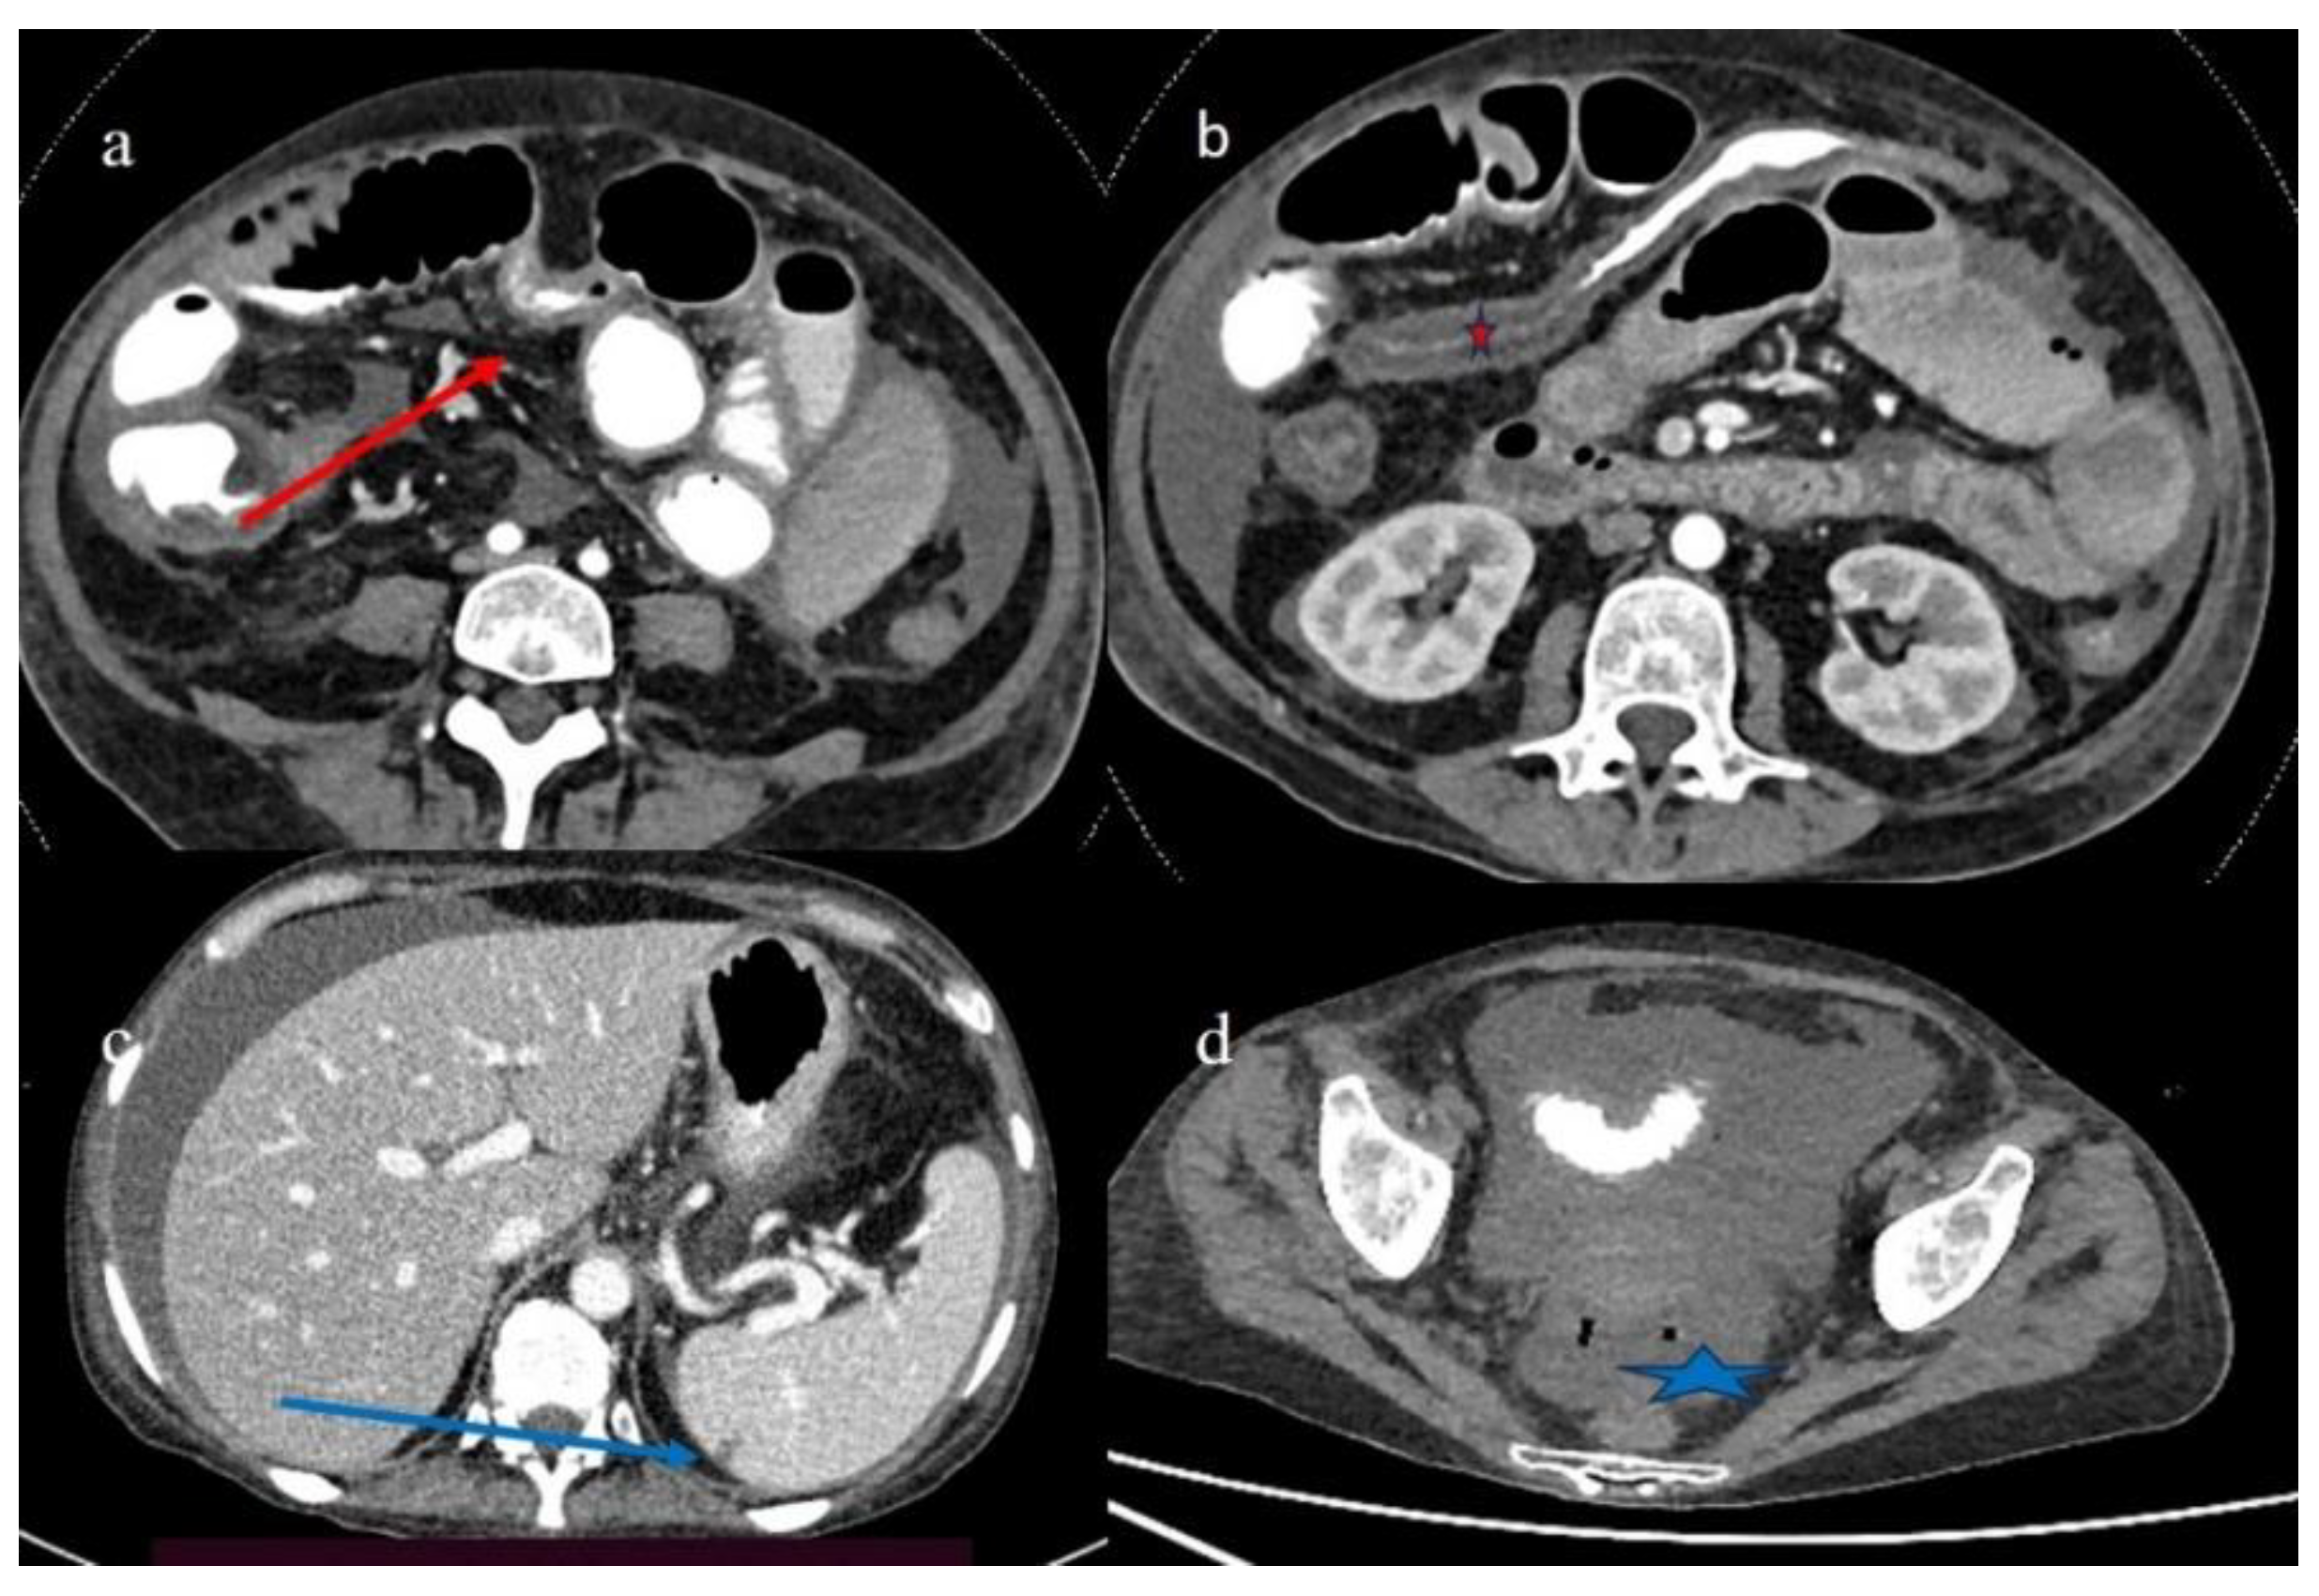

| 3 | P | P | Multisegmental thickness with stratified enhancement at the terminal ileus (on CECT control at 92 days). The CECT control at 129 days showed persistence of mild parietal thickness at terminal ileus and with mucosal enhancement | Diffuse parietal thickness with stratified enhancement (On CECT control at 92 days) The CECT control at 129 days showed colic fluid distension with mild diffuse mucosal enhancement | Diffuse comb sign, mild ascites, and poor reactive mesenteric lymph node | Hepatomegaly and mild gallbladder thickness |

| 4 | P | P | Intestinal diffuse homogeneous thickness with homogeneous mucosal enhancement (on CECT control at 66 days after the HSCT); diffuse small bowel involvement with increased parietal thickness on CECT control at 120 days | Appearance of multisegmental thickness on sigma and descending colon and stratified enhancement on transverse colon on the CT FU at 120 days | Diffuse comb sign and poor reactive mesenteric lymph node | Mild gallbladder thickness and persistence of biliary tract dilatation on follow-up CT |